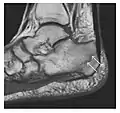

Triquetral fracture usually occurs on the dorsal aspect by impingement from the ulnar styloid or avulsion of strong ligamentous attachment. The dorsal avulsion fracture or "chip fracture" appears as a small bony fragment on the dorsal aspect of the triquetrum and is best detected on the lateral view(Figure 4). When radiography is negative in patients with high suspicion of a fracture, both MRI and MDCT will be of value. However, it has been shown that MRI is superior for detecting trabecular fractures in carpal bones.

a

b

Figure 4: Dorsal triquetral fracture of the left wrist in a 30-year-old man after a trauma. (a) Anteroposterior radiograph shows a normal appearance. (b) Lateral radiograph of the same wrist demonstrates a chip fracture off the dorsal aspect of the triquetrum (arrow).[1]